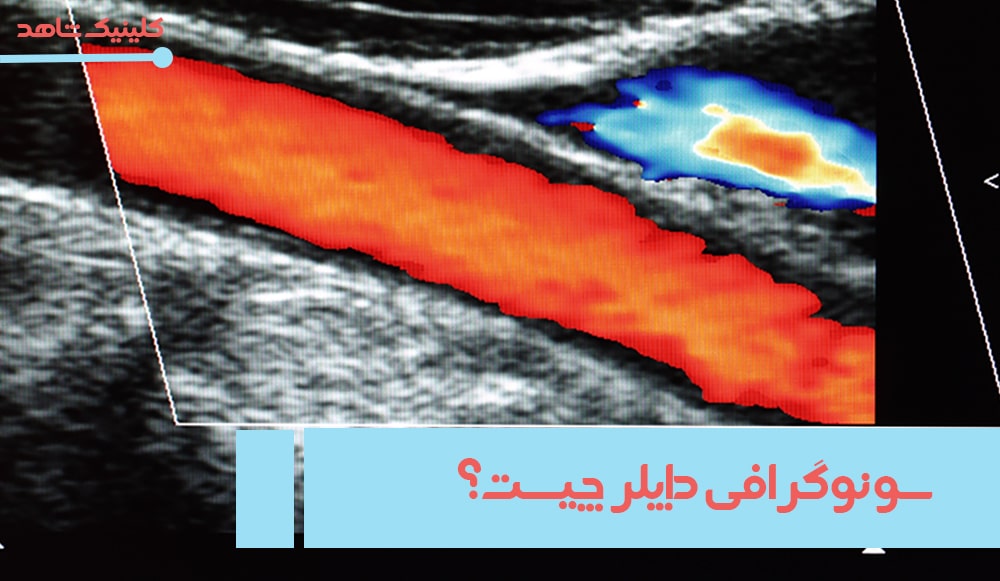

سونوگرافی داپلر عروق

با استفاده از سونوگرافی داپلر، جریان خون در رگ را مورد ارزیابی قرار می‌دهند. مشکلاتی مانند انسداد، گرفتگی و تنگی عروق، تومورهای خوش‌خیم و بدخیم با استفاده از سونوگرافی داپلر قابل تشخیص است.